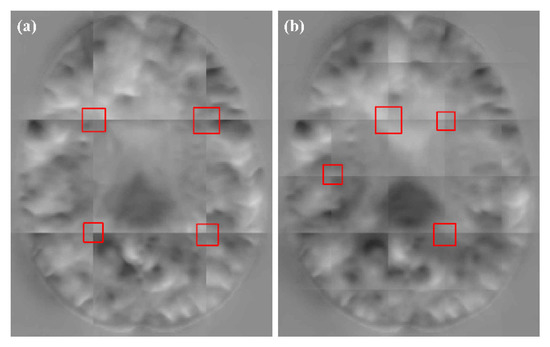

In Table 3, when the stride decreases, the smoothness of DDF increases with a smaller . However, the DSC of the CSF, GM and WM are nearly similar. As the number of patches increases with a small stride, the fusion time is significantly increased. Compared with the AAW method, the DSC and values of our method are higher than those obtained by AAW under different strides. We found that the stride had little effect on the obtained by our method, while the AAW method obtained a smoother deformation field with smaller strides. This further proves that our method can robustly maintain the predicted values of the registration model. In addition, the fusion times of the two methods has little difference. In Figure 10, we found that the DDFs of our method under different strides removed the grid-like artifacts, but the AAW method still has a small number of grid-like artifacts, even at a stride of 4 × 4 × 4. We can conclude that to obtain the DDF without grid-like artifacts, the AAW method requires a smaller stride while significantly increasing the fusion time. However, our method can obtain the DDF without grid-like artifacts in a shorter time, even under a larger stride, as well as a higher DSC value than that obtained by the AAW method.

Figure 10.

The results of different stride for AAW (a) and proposed method (b). The strides from left to right are 4 × 4 × 4, 8 × 8 × 8, 16 × 16 × 16 and 32 × 32 × 32.